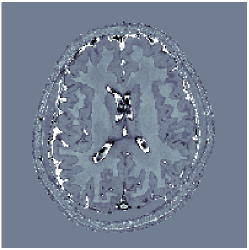

Two sets of experiments were conducted here: first, we used the 2D and 3D acquisition sequences for scanning a healthy volunteer’s brain (real-world acquisitions). Figures 6 and 7 display the parametric maps reconstructed from 2D spiral and radial readouts. We computed the T1, T2 and proton density (PD) maps using baseline reconstruction algorithms ZF, VS, LR, FLOR, AIR-MRF and our proposed LRTV. While baselines use DM either for quantitative inference or also during reconstruction (i.e. AIR-MRF), we further compare the DM-free LRTV’s performance when cascaded to DM, KM and MRFResnet for quantitative inference. For the 3D spiral acquisitions we compared LRTV and its closest competitor VS in Figure 8. Outcomes from other tested algorithm are displayed in the supplementary materials (Figure S5). Since FLOR does not use dimensionality-reduction, our system ran out of memory during 3D reconstruction; hence results are not reported in this case.

VI-E1 Discussion

The LRTV-DM and LRTV-MRFResnet perform on par, and both outperform all tested baselines for reconstructing T1, T2 and PD maps in all acquisition schemes. This can be observed both visually in Figures 6, 7, 8, S2 and S3, and quantitatively in Table IV across all tested metrics. Other baselines were unable to successfully remove the under-sampling artefacts in TSMIs, and these errors propagated to the parameter inference phase and resulted in inaccurate maps. Temporal-only priors incorporated within LR are shown insufficient to regularise the inverse problem and LR sometimes (e.g. 2D spiral acquisitions) can admit solutions with even stronger artefacts than the model-free ZF baseline. This issue was previously studied for other non-Cartesian MRF readouts that similar to our spiral/radial trajectories, miss to sample the corners of the k-space in all timeframes (see section 2.2.2 and figure 2 in [19]). In the absence of reference for the k-space corners information, the LR iterations despite minimising the objective can converge to solutions with high-frequency artefacts, as visible in the computed maps. This highlights the need for adding an appropriate spatial-domain regularisation. FLOR reduces the LR’s artefacts but this improvement is limited because the suggested nuclear norm penalty does not incorporate an explicit spatial regularisation. Further for reducing artefacts, FLOR can introduce an undesirable bias in the computed T1/T2 maps e.g. see error maps in Figures S2 and S3. The non model-based VS baseline incorporates spatial regularisation and results in spatially smoother maps than ZF and LR, but it is unable to output artefact-free images. Further and consistent with our in-vitro experiment, we observe that VS overestimates the T2 values (e.g. in White and Grey matter regions) in tested 2D acquisitions i.e. the spatial regularisation trades off agains the quantification accuracy. The model-based AIR-MRF adds spatial regularisation through 2D/3D low-pass Gaussian filters however this trades off the sharpness of the computed maps and can increase the errors at the tissue boundaries (we searched Gaussian spreads that keep the blurs and high-frequency artefacts minimal). For our acquisition readouts, Gaussian filters performed better than disk filters of [19] for avoiding strong Gibbs artefacts. On the other hand, the spatiotemporally regularised LRTV greatly improves the TSMI reconstructions i.e. 4 dB enhancement compared to the closest competitor baseline (Table IV). This enables computing accurate and aliased-free multi-parametric inference using DM or the DM-free learning-based alternative MRFResnet as visible in Figures 6, 7, 8, S2 and S3. MRResnet and DM score competitive quantitative inference results i.e. T1 and T2 MAPE less than 5% and 9%, respectively (Table IV). KM also outputs comparably accurate T1 maps, however this shallow learning model despite having a model size larger than MRFResnet, is unable to learn accurate T2/PD quantification and it results in poor estimated maps, consistent with our observations in section VI-C.